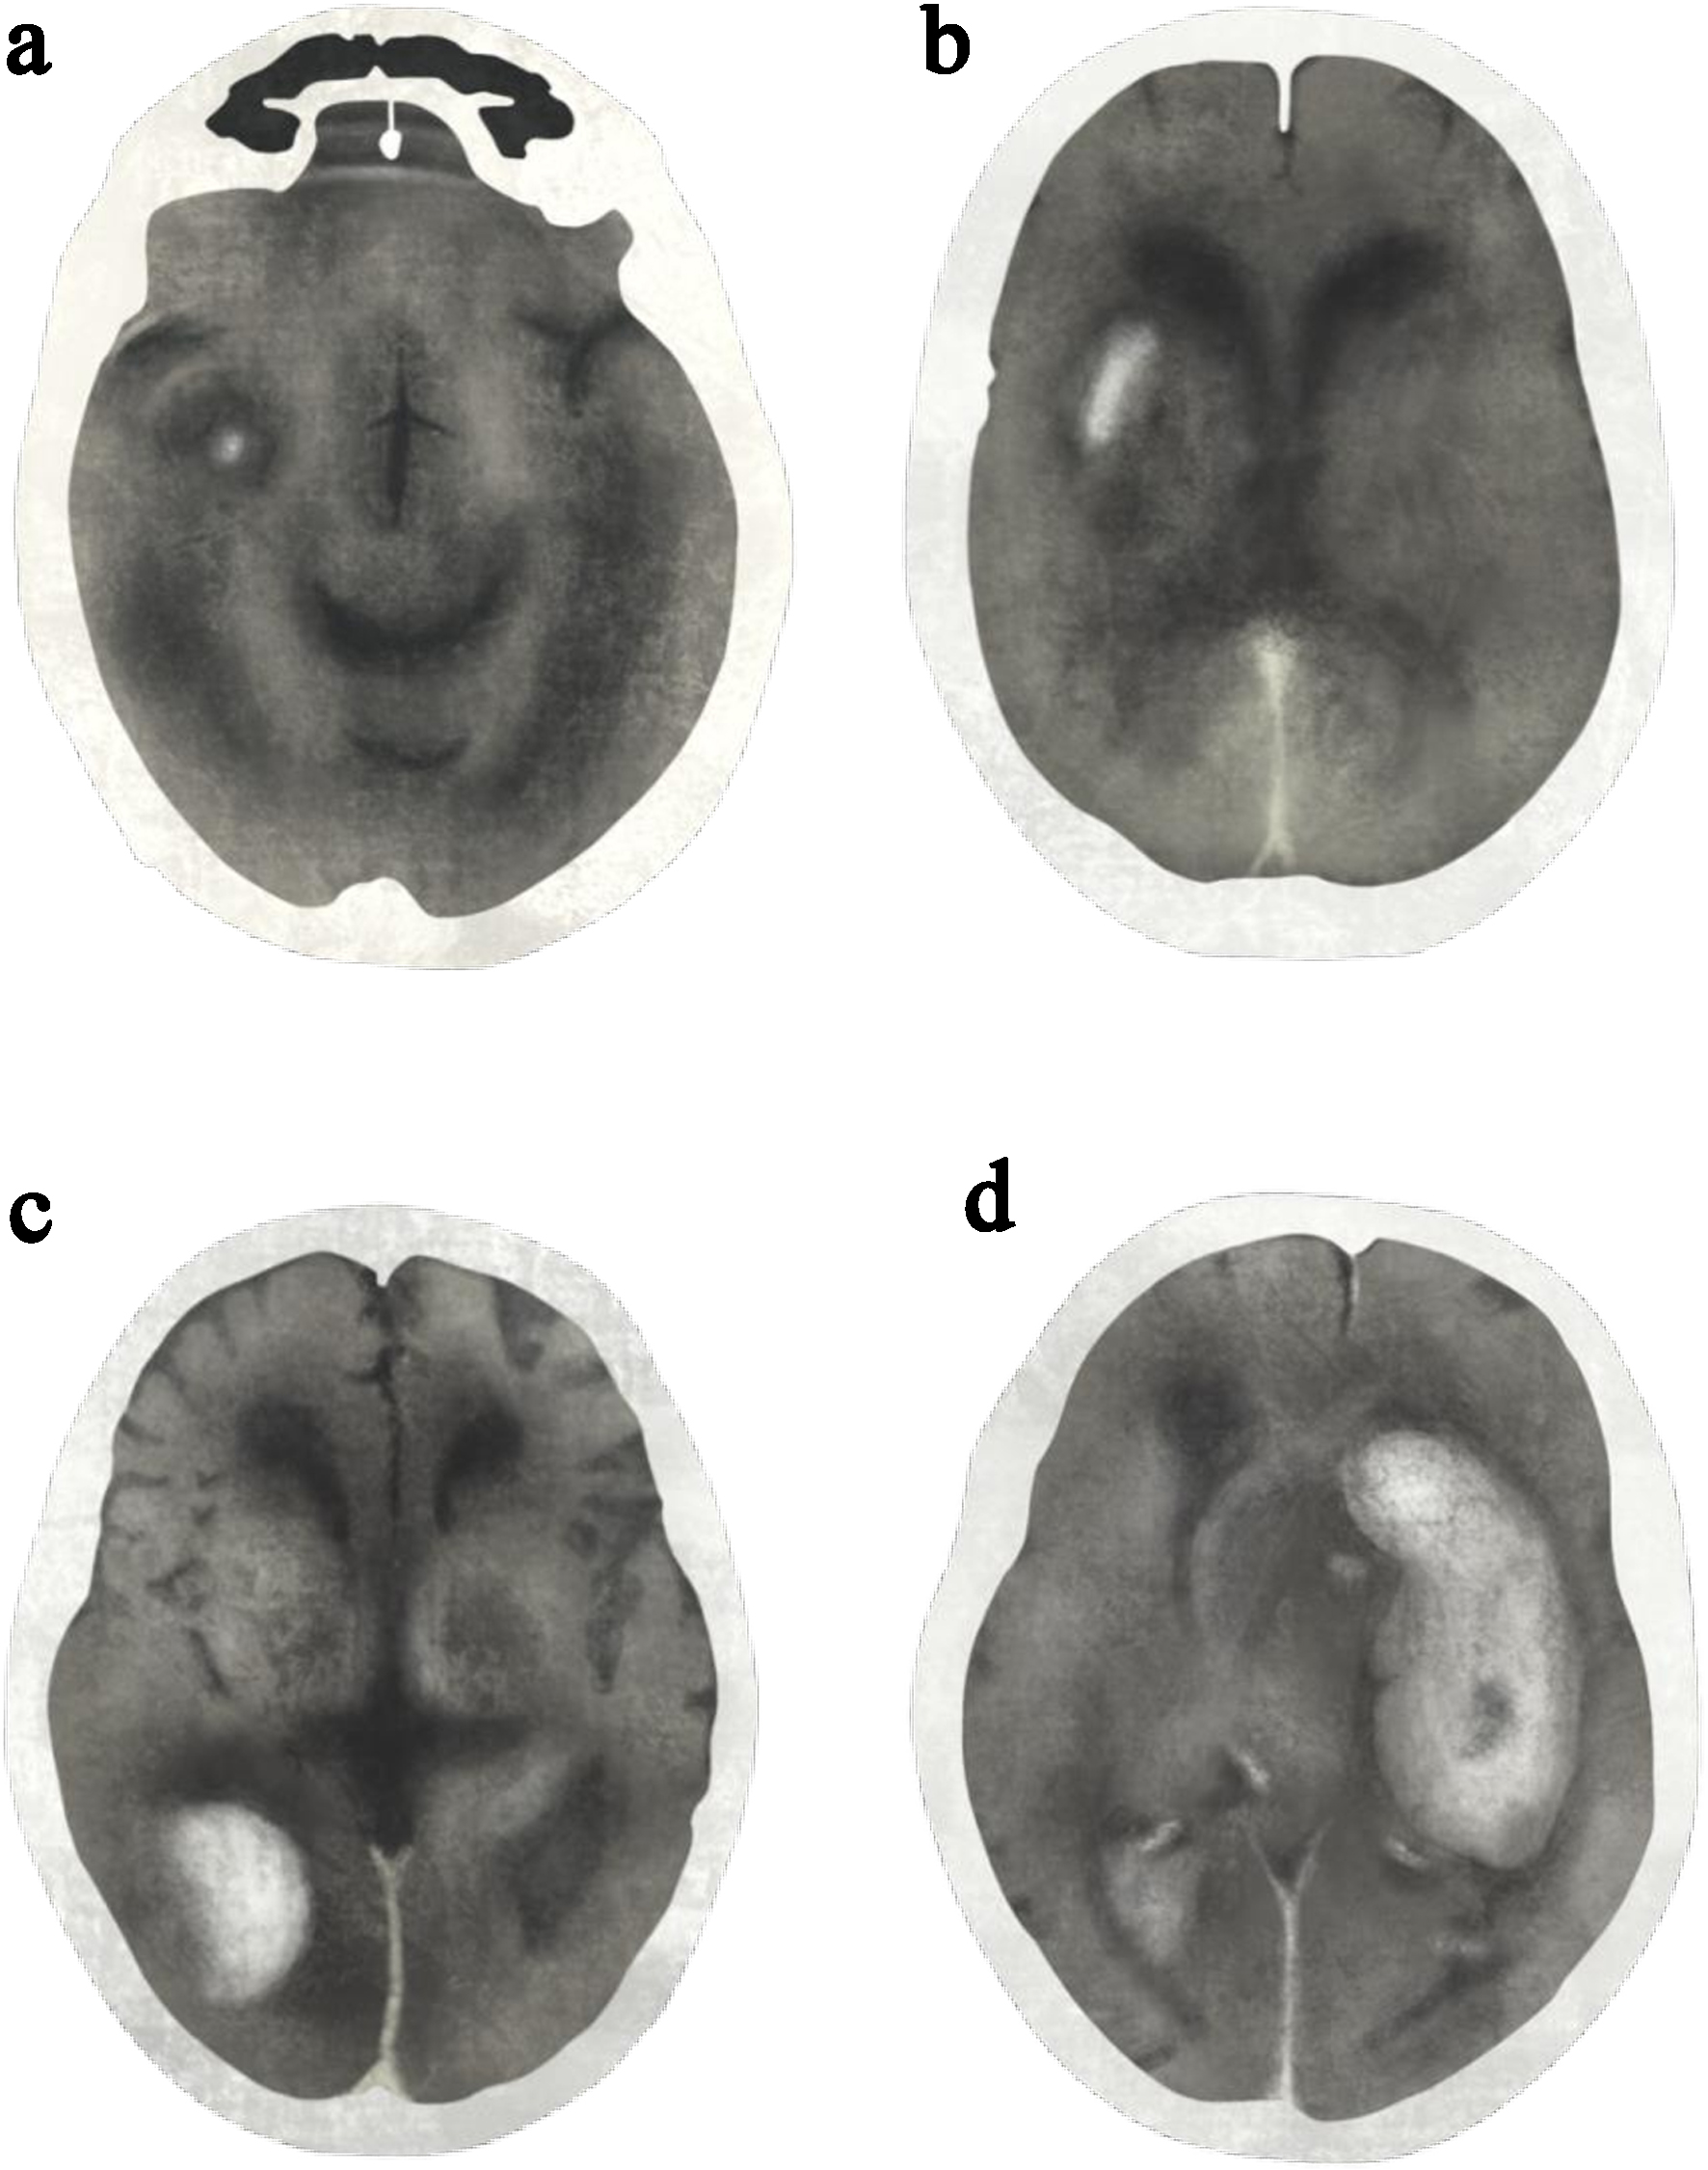

Radiographic classification [16] includes: 1) HI1: small petechial hemorrhages at the infarct margins, without mass effect. 2) HI2: confluent petechial hemorrhages throughout the infarcted region, without mass effect. 3) PH1: hematoma involving ≤ 30% of the infarcted area, with mild mass effect. 4) PH2: hematoma involving > 30% of the infarcted area, with substantial mass effect (Fig. 1).

Figure 1. Post-alteplase intracerebral hemorrhage classified by radiographic classifications: (a) hemorrhagic infarction type 1 (HI1), (b) hemorrhagic infarction type 2 (HI2), (c) parenchymal hematoma type 1 (PH1), and (d) parenchymal hematoma type 2 (PH2). Illustration drawn and modified from the original reference [16].